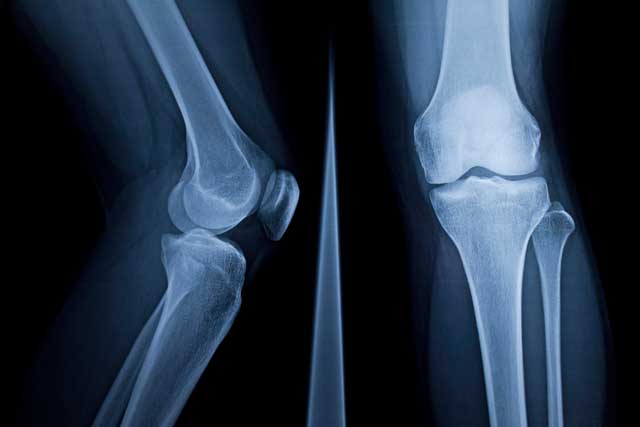

Hip and Knee Service

Problems affecting the hips or knees, such as osteoarthritis, cause significant pain and loss of function to a large number of people. The good news is that we have the ability to help.

Our Hip and Knee Service is dedicated to the diagnosis, investigation and treatment of all types of hip and knee problems deriving from: